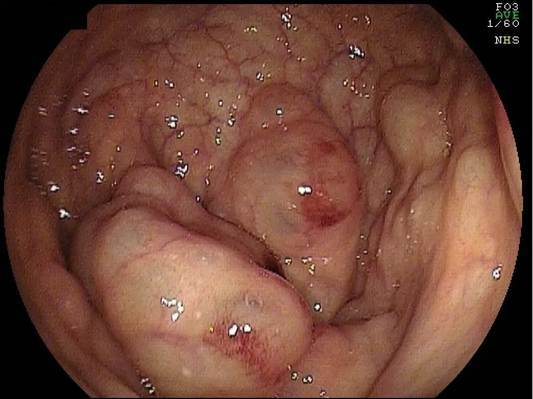

Pneumatosis Coli: Characteristics, Diagnosis, a...

An elderly patient presented with abdominal pain, diarrhea, and fever. A colonoscopy found pneumastosis coli in sigmoid colon polypoid lesions ranging from 10 to 30mm in size. This article describes...